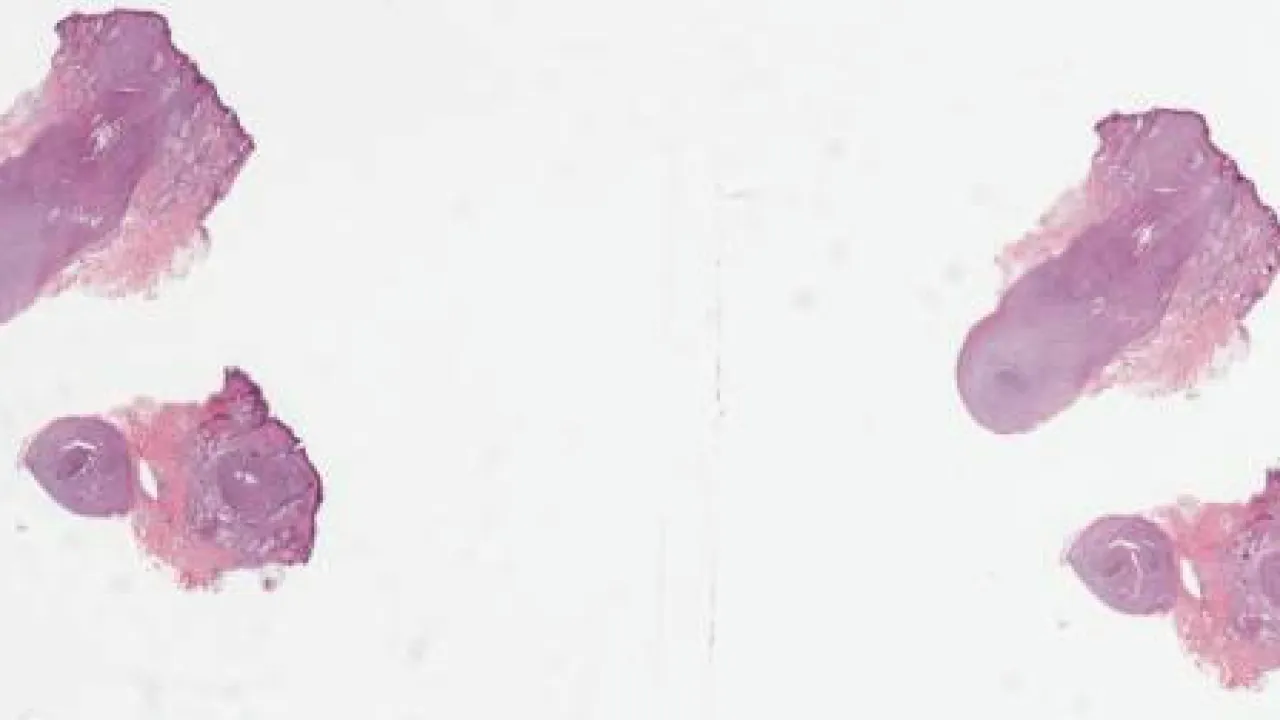

Brain, Pineocytoma